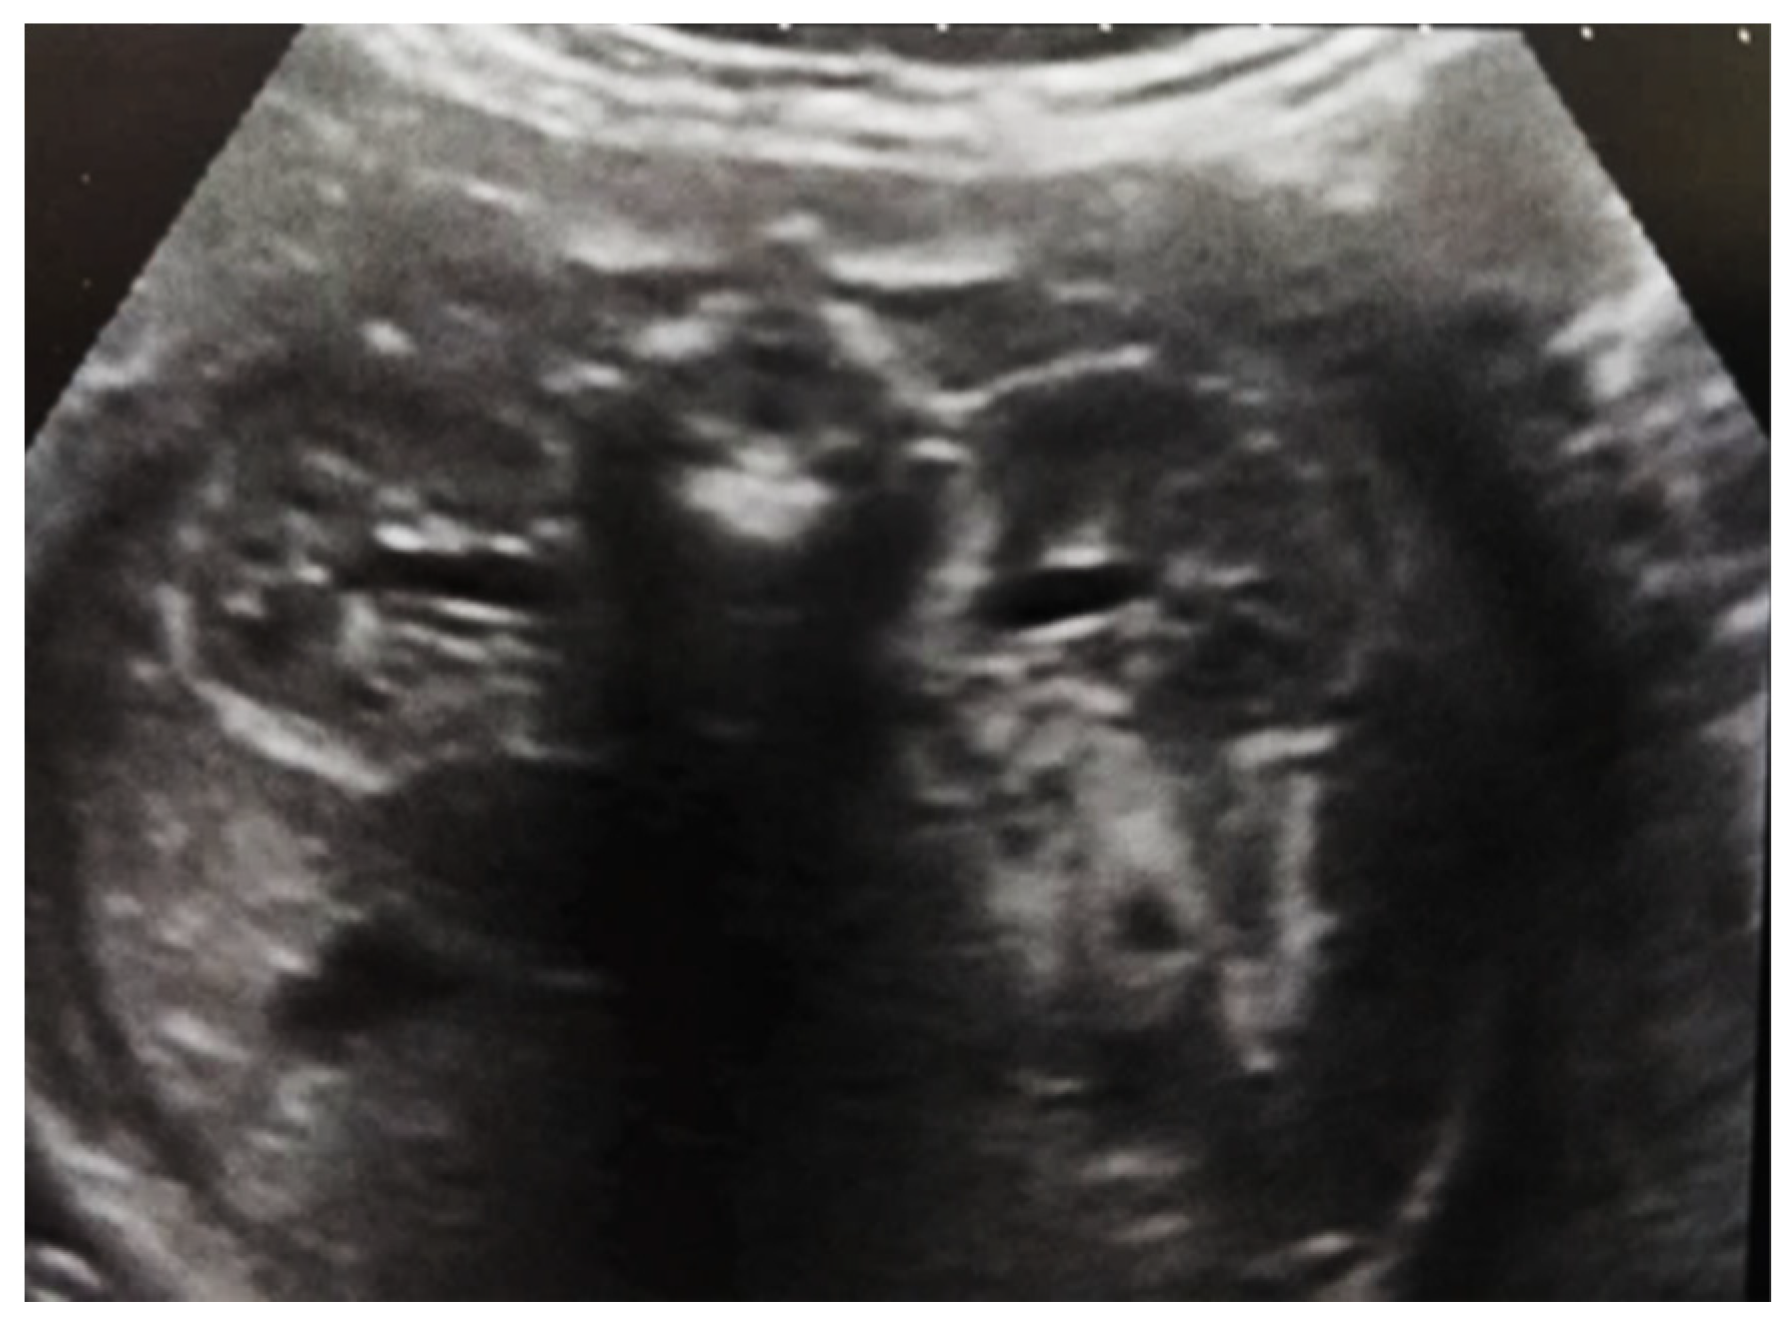

Figure 9. Ultrasound of the urinary system in a 12-day-old newborn. Hydrocalconephrosis on the left (a) and ureteral hydronephrosis on the right (b).

Our experience with congenital malformations of the urinary system refers to the following clinical case (Figure 2, Figure 3, Figure 4, Figure 5, Figure 6, Figure 7, Figure 8 and Figure 9). In the first case, during pregnancy, the 21-week ultrasound determined bilateral renal pyelectasia. The fetus had hydronephrosis on the right; at 31 weeks, it had bilateral hydrocalconephrosis; and at 32 weeks, bilateral pyelectasia. It suffered premature birth at 36 weeks, with complicated anomalies of the forces of contraction, prolonged birth, and birth weight of 2200 g. Postnatal ultrasonography was supplemented by intravenous urography, and bilateral hydronephrosis was determined. Hydrocalconephrosis on the left was discovered. The complete diagnosis was established: congenital renal malformation; bilateral pyelectasia; bilateral hydronephrosis; hydrocalconephrosis on the left; and severe reduced glomerular filtration rate (GFR), GFR > 2SD below mean.